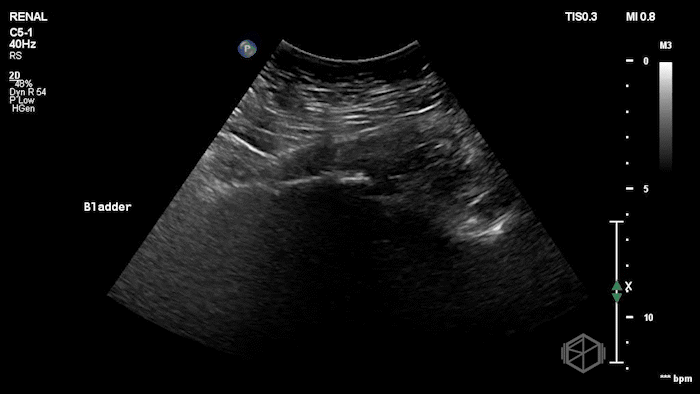

Several days later, she returned to the ED with hypotension, lightheadedness, and mild abdominal discomfort. Recognizing the potential urgency, Dr. Weinberger immediately performed a POCUS, which revealed the following:

The patient had complex free fluid in the abdomen, noted with septations and fibrinous stranding. Surgery was immediately notified and a CT was performed a little while later that showed a moderate amount of free air in the abdomen, fluid suspicious for peritonitis, and concern for a leak at the small bowel connection in the right lower quadrant. In surgery, cloudy bile-tinged fluid was found but no stool. The previous connection had poor blood flow and a small leak. That section was removed, a new connection was made between healthy bowel, and the abdomen was closed. The patient tolerated the procedure and did well.